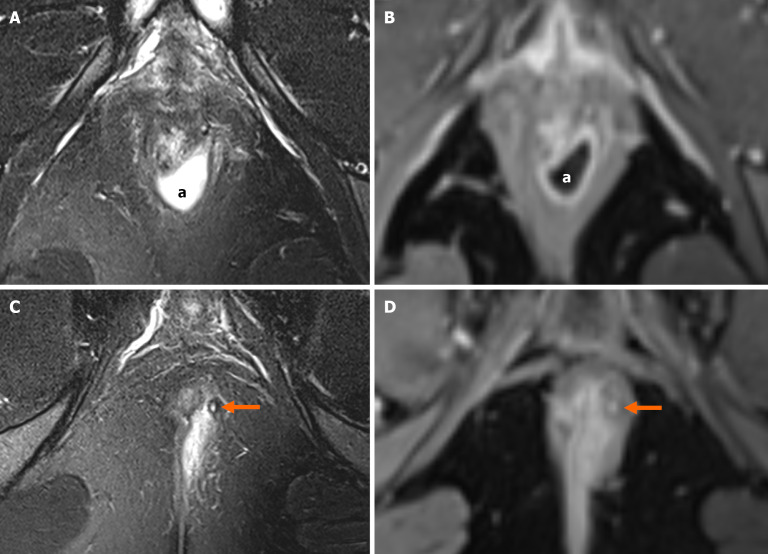

Perianal fistulising Crohn's disease is a challenging complication that can affect up to 20% of patients with Crohn's disease and is associated with significant morbidity. Despite advances in medical therapies, particularly anti-tumor necrosis factor agents, the majority of patients still require surgical intervention. Accurate diagnosis and monitoring are essential to optimise outcomes and guide multidisciplinary management. Although clinical scoring systems such as the perianal disease activity index are widely used, their subjective application limits their reproducibility and reliability, underscoring the need for more objective methods of evaluating perianal fistulising Crohn's disease activity. Imaging has thus become central to the objective assessment of perianal fistulising Crohn's disease, with magnetic resonance imaging (MRI) recognised as the gold standard in view of its ability to provide clear, detailed images of the perianal region in a radiation-free manner. Guidelines also endorse the use of imaging modalities such as endoanal ultrasound and transperineal ultrasound as viable alternatives to MRI for the assessment of perianal fistulising Crohn's disease in centres with appropriate expertise. This article aims to evaluate and compare the diagnostic accuracy and clinical utility of MRI, endoanal ultrasound, and transperineal ultrasound in the assessment of perianal fistulising Crohn's disease, highlighting their respective strengths, limitations, and roles in clinical practice.